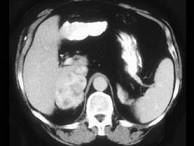

问题 女,32岁,阵发性高血压2年余,请结合所提供图像,作出诊断 ( )

选项 A、左肾上腺嗜铬细胞瘤 B、左肾上腺淋巴瘤 C、左肾上腺腺癌 D、左肾上腺转移瘤 E、左肾上腺腺瘤

答案 A